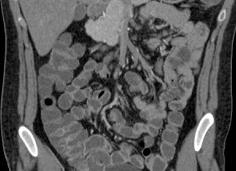

МРТ коленных суставов

Коленный сустав очень уязвим. Ему приходится выдерживать значительные динамические нагрузки. Болевой синдром в коленях беспокоит многих людей, но чаще всего с ним сталкиваются спортсмены и люди преклонного возраста. Иногда для выяснения причины появления болей и хромоты не обойтись без МРТ коленного сустава. Поэтому пациенты хотят знать, что такое МРТ коленного сустава и как его делают.